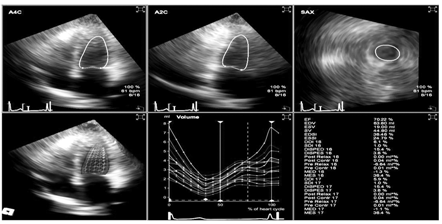

实时三维超声心动图测量左室非同步化指数的重复性及再现性评价